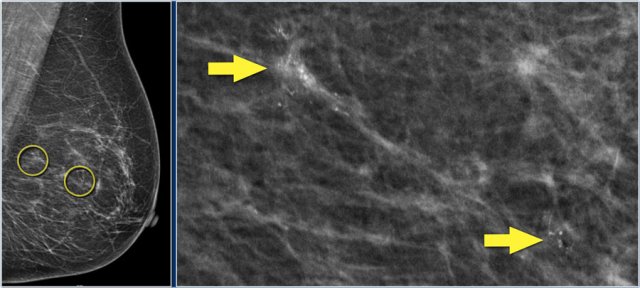

In this patient, there are two groups of suspicious calcifications which are about 5 cm apart.

First the larger group was biopsied.

The idea was that if these calcifications were benign, then the smaller cluster would probably also be benign.

However, the larger group of calcifications turned out to be DCIS grade 2.

So a second biopsy was needed of the smaller group of calcifications, and this also turned out to be DCIS grade 2.

A mastectomy with a sentinel node procedure was planned.

The total area of DCIS was thought to be too large for breast conserving treatment.